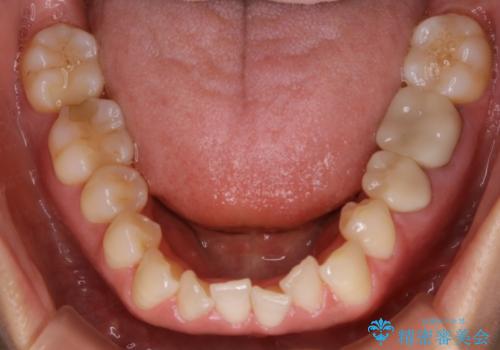

- 歯のガタつきによる見栄えや清掃困難を主訴にご来院されました。

左側の噛み合わせは上の歯が前方に寄ってきてしまっていることが原因のズレがありました。

ガタつき自体は歯列の幅の拡大やディスキング(IPR)でほとんど解消可能でしたが、噛み合わせのズレは歯の移動が必要だったため、左上にマイクロインプラントを使用し噛み合わせの改善とガタつきの解消を同時に進めるという方針をとりました。

歯列弓の拡大

歯並びが悪くなる原因の一つに「歯列弓の狭窄」というものがあります。

奥歯や前歯が内側(舌側)に倒れ込んでしまったり、歯が生えてくる位置が内側になってしまうことにより歯並びのアーチが狭くなってしまうことを言います。

このような場合、歯並びのアーチを拡大してあげるだけでもガタつきを無くすためのスペースがかなり作れることがあります。